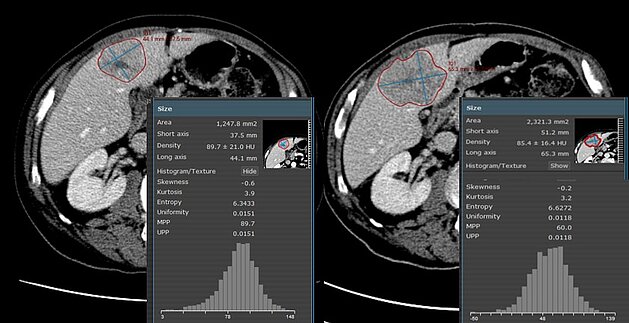

The benefits that texture analysis and radiomics have shown already, and the improved availability of large data sets led to an increased interest in…

In a retrospective study [1], a team from Royal Marsden in London and Sutton explored changes of CT texture analysis metrics in unresectable liver…